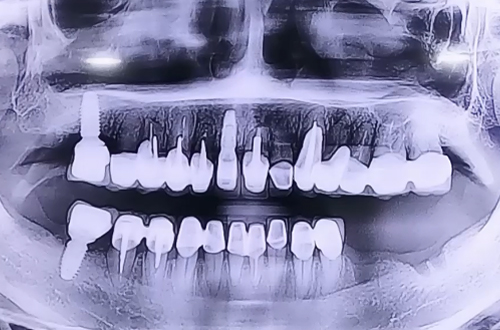

BEFORE

치료 유형 아랫니 뼈이식 임플란트

왼쪽 아래 발치한 부분에 임플란트를 이용하여 다시 회복시킬 계획으로 병원에 방문하신 환자분이십니다.

발치되어 있는 부분의 잇몸이 많이 내려가 있는 케이스로 임플란트를 심으면서 눌릴 가능성이 높아 신경 바로 위까지만 임플란트를 심고 나머지 부위들은 주변으로 뼈이식을 병행하여 꼼꼼하게 진행해 드렸습니다.

신경 바로 위쪽으로 임플란트 두 개를 안전하게 심으며 양쪽 임플란트를 브릿지 형태로 왼쪽 아래 보철을 완성 시킬 계획입니다.